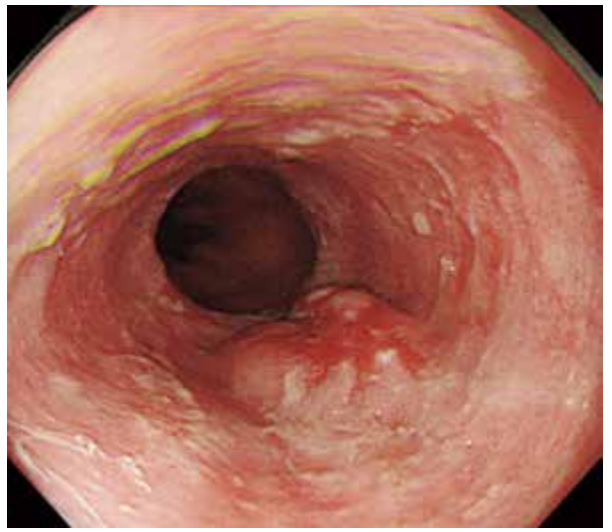

●背景黏膜血管透见性差,局部黏膜粗糙。在胸部下段食管后壁,见一中央伴有凹陷的平缓隆起性病变。

●通过减少空气量,观察病变,并没有发现病变形态改变,考虑病变整体较厚、较硬(→)。

图片右侧为口侧。在黏膜平缓隆起的中央,观察到不规则的发红凹陷。